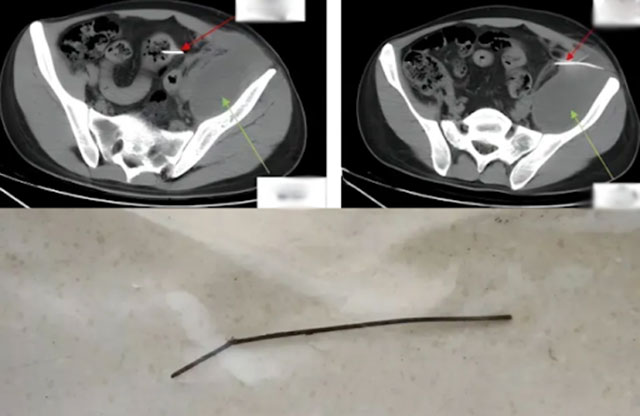

Tại đây, Phó trưởng khoa Ngoại Tổng hợp Cao Yanbing thực hiện chụp CT bụng cho Tiểu Thiện và phát hiện dị vật lớn đã mắc kẹt lâu ngày, gây viêm nhiễm và thủng ruột. “Dị vật dài 13cm, một đầu nhọn, đã xuyên qua thành ruột, tạo mủ lớn sau phúc mạc. Phẫu thuật là cần thiết ngay lập tức" - bác sĩ Cao cho biết.

Ca phẫu thuật kéo dài 2 giờ 40 phút bằng phương pháp nội soi. Các bác sĩ lấy ra một xiên kim loại dài 13cm, thường dùng để xiên thịt nướng. Chiếc xiên đã xuyên qua đại tràng sigma, vào phúc mạc bên trái, có dấu hiệu rỉ sét. Sau khi lấy dị vật, bác sĩ xử lý áp xe phúc mạc, hố chậu và loại bỏ 180ml mủ hôi thối trước khi khâu lại ruột.